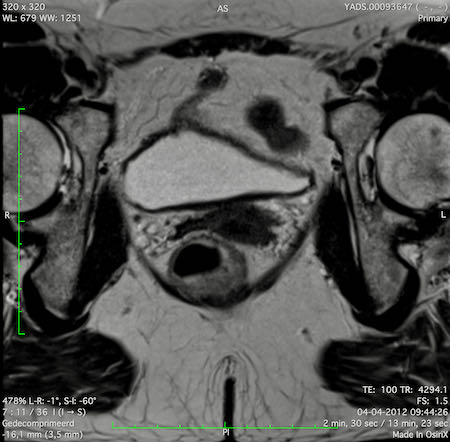

Hình ảnh

Các hình ảnh được cung cấp cho thấy ung thư biểu mô tế bào nhẫn với tình trạng dày lan tỏa thành trực tràng, hình ảnh bia bắn điển hình, và sự xâm lấn mỡ mạc treo trực tràng.